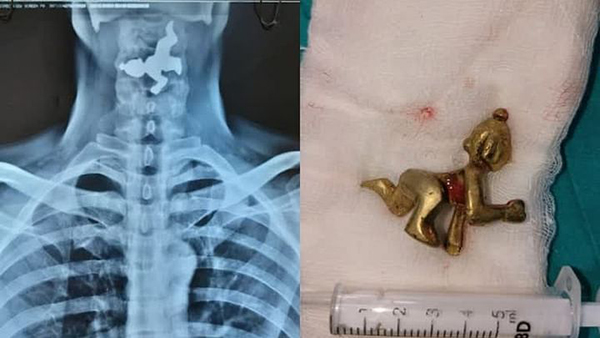

கர்நாடக மாநிலம் பெலகவி மாவட்டத்தில், 45 வயது மிக்க நபர் ஒருவர் தனக்கு தொண்டை வலி இருப்பதோடு மூச்சு விடுவதில் சிரமம் இருப்பதாக கூறி தனியார் மருத்துவமனையை அணுகினார். எனவே அங்குள்ள மருத்துவர்கள் அவருக்கு X-Ray எடுத்து பரிசோதனை செய்தனர். X-Ray ரிப்போர்ட்டை பார்த்த மருத்துவர்கள் அதிர்ச்சியடைந்தனர்.

அதில், அவரது தொண்டையிலுள்ள உணவு குழாயில் இரும்பு வடிவிலான பொருள் ஒன்று சிக்கியுள்ளது தெரிந்தது. பின்னர் இது குறித்து அவரிடம் விசாரித்த போது, தான் எதையும் உட்கோள்ளவில்லை என்று தெரிவித்தார். தொடர்ந்து அவரிடம் கேட்கையில், தான் வழக்கமாக அருகிலிருக்கும் ஒரு கோயிலில் நீராடி, அந்த நீரை பருகுவதாக தெரிவித்தார்.

இதனையடுத்து, அவருக்கு ENDOSCOPY என்ற சிகிச்சை மூலம் தொண்டையில் சிக்கியிருந்த பொருளை தொண்டை வழியே வெளியே எடுத்தனர். இது குறித்து மருத்துவர்கள் கூறுகையில், 45 வயது மதிக்கத்தக்க நபர் ஒருவர் தனக்கு மூச்சு விடுவதில் சிரமமாக இருப்பதாக அணுகினார்.

அவரை பரிசோதனை செய்ததில், தொண்டையில் பொருள் இருப்பது கண்டுபிடிக்கப்பட்டு, சிகிச்சை மூலம் வெளியே எடுக்கப்பட்டது.

இந்த சிகிச்சையின்போது உணவுக் குழாயில் சிலையின் இடது கால் சிக்கிக் கொண்டதால் எங்களுக்கு மிகவும் கடினமாகவும் சவாலாக இருந்தது. எனவே எதை சாப்பிட வேண்டுமென்றால் பார்த்து சாப்பிடுங்கள், பருகுங்கள்” என்றனர்.